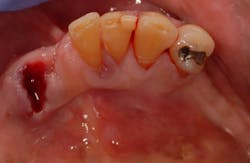

A 62-year-old African-American male presents for extraction of all remaining mandibular teeth, as well as placement of an implant-supported overdenture. At presentation, the patient’s health is noncontributory. The existing teeth have extensive periodontitis with a hopeless prognosis. Tooth No. 22 has Class III mobility and is removed prior to beginning treatment (figure 1).

Figure 1: Pre-op